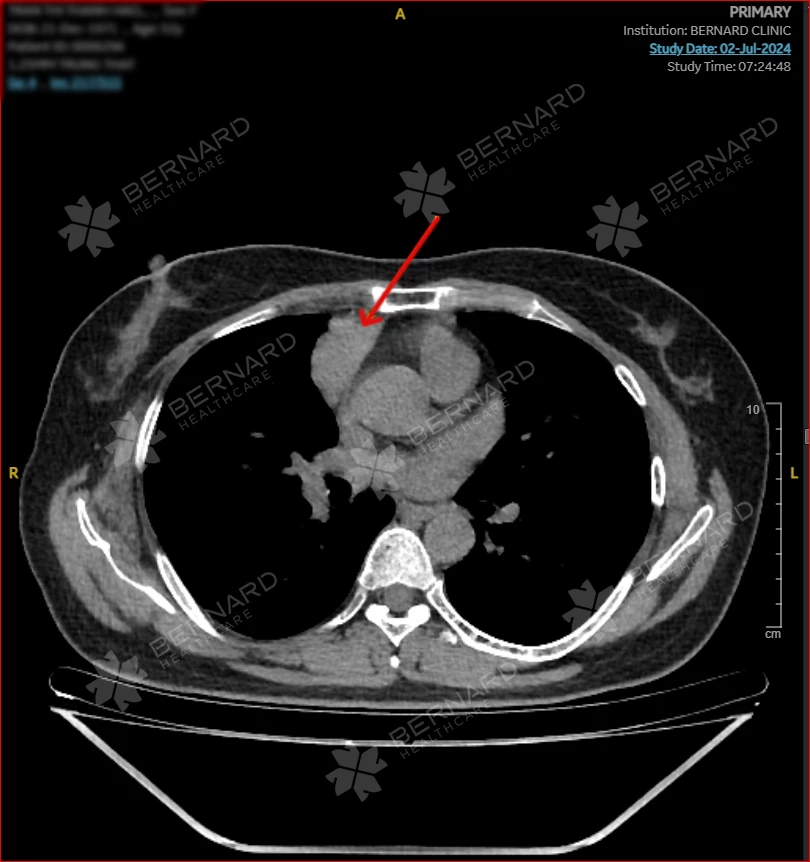

Sau đó, chị H. được chỉ định thực hiện các xét nghiệm và một số cận lâm sàng chuyên sâu cần thiết, trong đó có chụp CT lồng ngực. Kết quả phim chụp ghi nhận có một tổn thương bất thường ở phổi.

Cụ thể:

- Có cấu trúc choán chỗ trung thất trước cạnh phải (P) tim, đường kính (d) 2.2 x 4.0 cm, đậm độ trung bình, bắt quang trung bình, không đồng nhất.

- Khối bất thường trên chưa cho thấy có sự thấy xâm lấn tổn thương vào các cấu trúc lân cận.

Từ đây, Bác sĩ Bernard nghĩ nhiều đến U tuyến ức bao gồm U Thymoma, không loại trừ U Lymphoma.